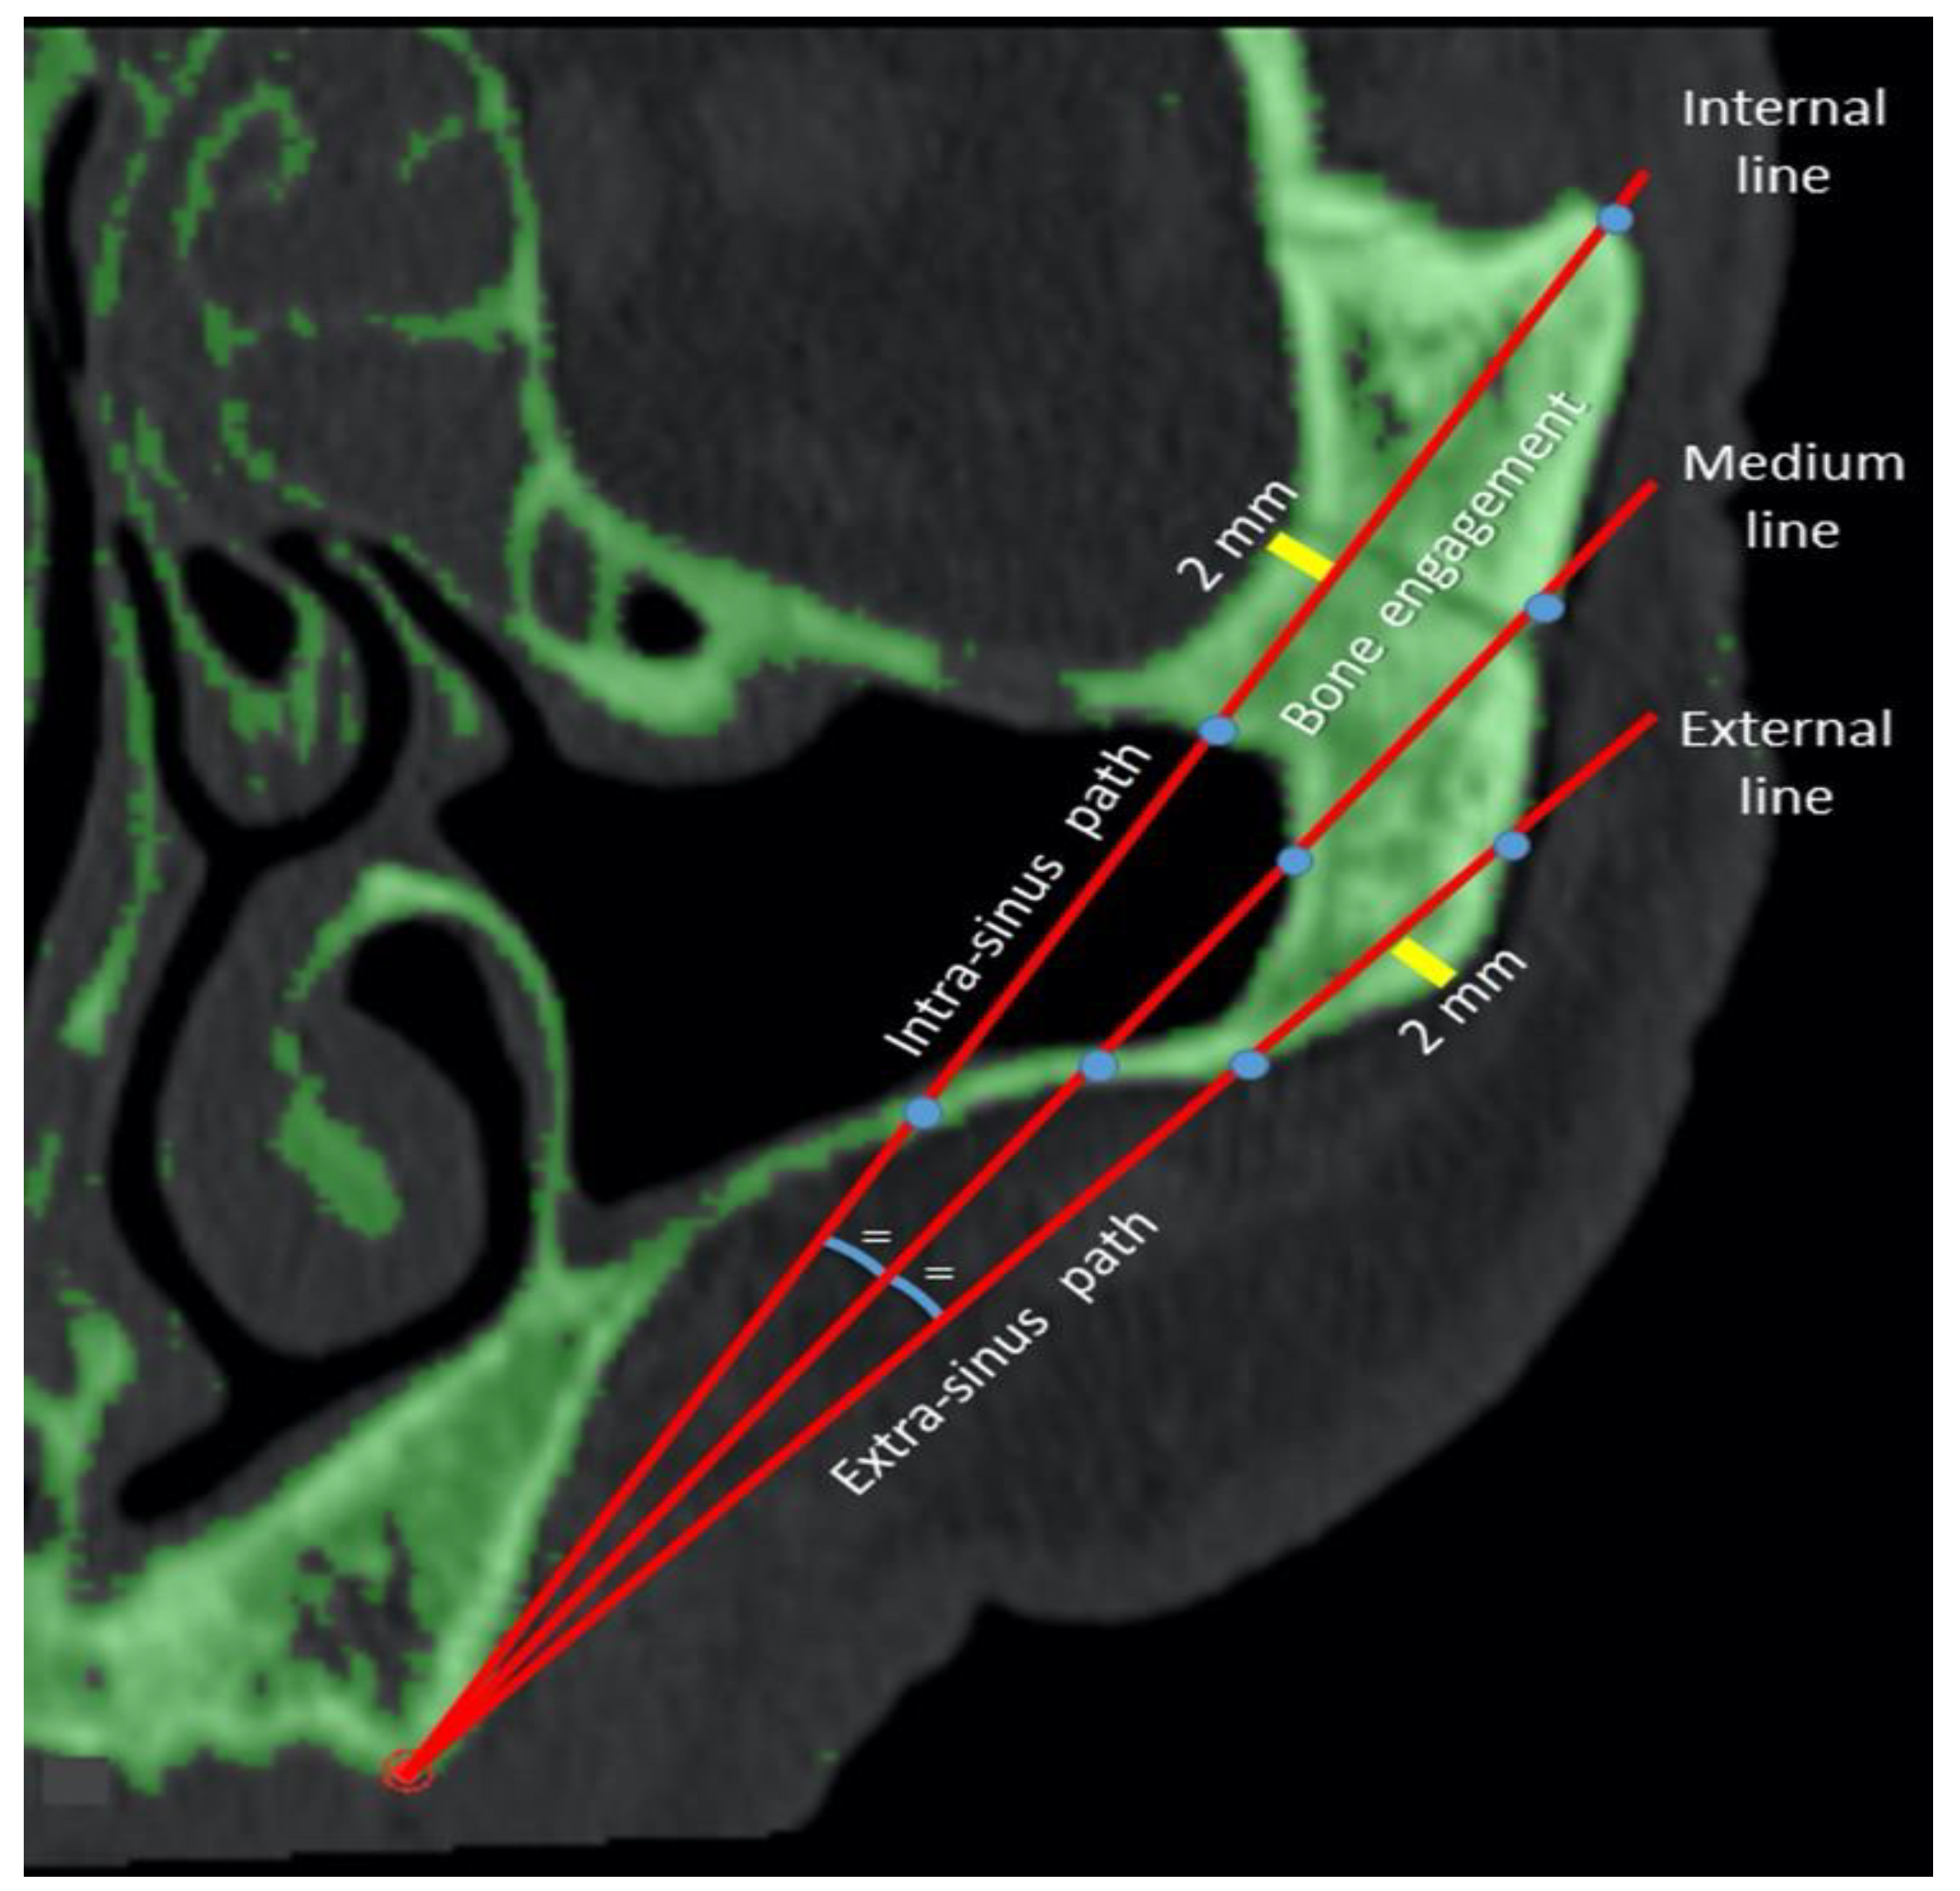

2.3. Measurements of the Zygomatic Bone

3. Results

3.2. Phase 2